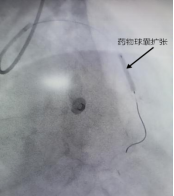

一位中年男性,因“胸闷气促”入院,此次发病后冠脉造影提示前降支中远段狭窄80%。心内科团队经过精准评估后发现,患者血管直径只有2.5mm,没有植入新支架,而是用药物球囊扩张成形术解决问题。手术成功打通狭窄血管,实现血运重建,患者体内未增加任何金属异物,有效缓解了患者病痛。